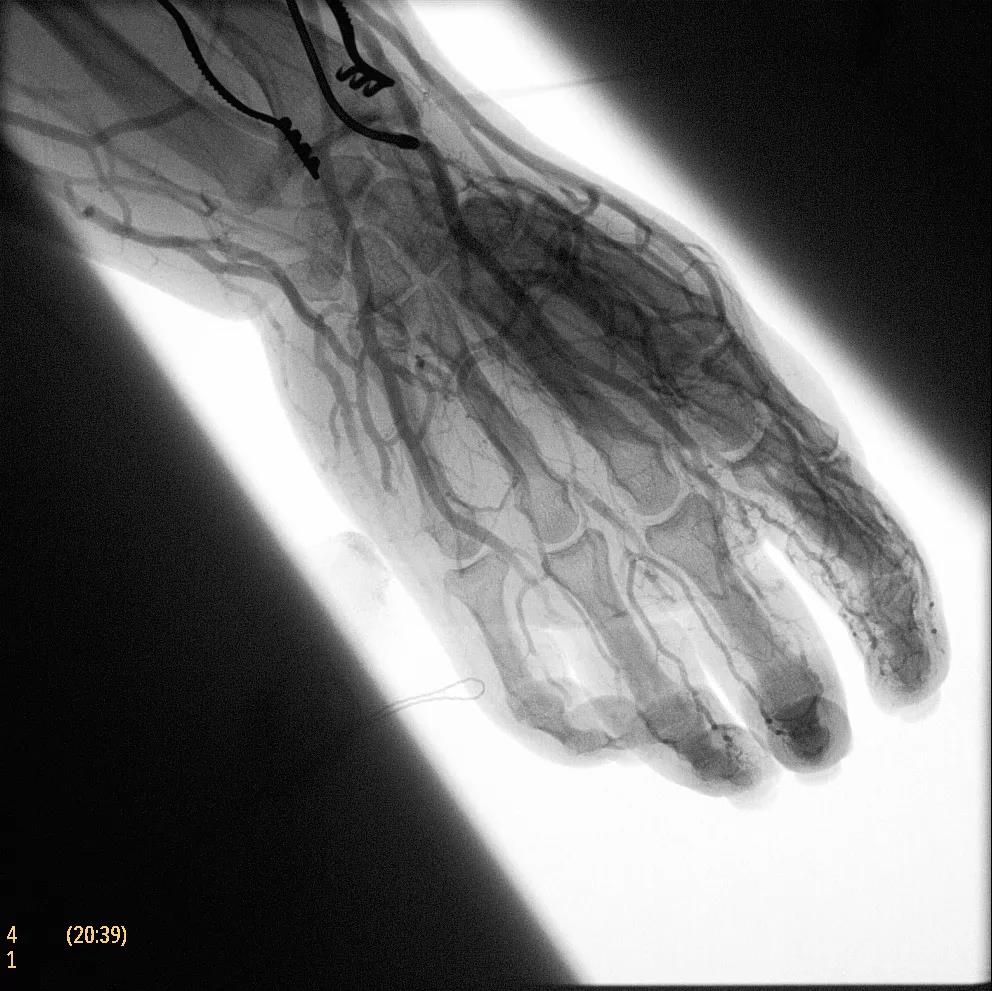

飛利浦于2019年2月18日宣布推出帶扁平探測(cè)器的移動(dòng)式C臂Zenition 70。Zenition 70使用飛利浦第四代Flat Detector系統(tǒng),具有卓越的成像清晰度和靈活性,可執(zhí)行各種情況。

據(jù)器械之家了解到,移動(dòng)式C型臂是X射線系統(tǒng),可帶入手術(shù)室(OR),在整形外科、創(chuàng)傷和血管手術(shù)等各種手術(shù)過程中提供實(shí)時(shí)圖像引導(dǎo)。Zenition70使醫(yī)院能夠最大限度地提高OR性能,增強(qiáng)臨床能力并為員工提供高質(zhì)量的用戶體驗(yàn)。

( Zenition 70匯集了圖像捕獲,圖像處理,易用性和多功能性方面的創(chuàng)新。)

在快速增長(zhǎng)的圖像引導(dǎo)微創(chuàng)手術(shù)領(lǐng)域 ,手術(shù)干預(yù)的范圍和復(fù)雜性在繼續(xù)增加,需要治療的患者數(shù)量也在增加。為了以更低的成本治療更多的患者,醫(yī)院需要具有不同能力的多功能C臂組,以便容易地適應(yīng)不同類型的手術(shù)和不同操作者的需要。Zenition 70易于在手術(shù)室之間移動(dòng),易于在患者周圍定位并且操作直觀。

飛利浦Zenition 70支持整個(gè)醫(yī)療保健機(jī)構(gòu)提高OR性能。平臺(tái)類似平板電腦的用戶界面和簡(jiǎn)單的統(tǒng)一工作流程意味著一旦操作員學(xué)會(huì)在平臺(tái)上使用一個(gè)系統(tǒng),他們就可以輕松地操作它們。該系統(tǒng)可在任何介入或外科手術(shù)過程中快速直觀地拍攝傻瓜相機(jī)。Zenition的緊湊設(shè)計(jì),位置記憶功能(僅適用于Zenition 70)和BodySmart軟件,即使在圖像增強(qiáng)器或平板探測(cè)器的邊緣也能捕捉快速一致的圖像,將C臂重新定位的需求減少45%。

( Zenition 70采用與Azurion平臺(tái)相同的圖像處理算法。

為了獲得清晰的高質(zhì)量圖像,Zenition 70 采用了與公司Azurion平臺(tái)相同的圖像處理算法,可提供患者解剖結(jié)構(gòu)的高清可視化和更大的可視區(qū)域。飛利浦的MetalSmart軟件等功能可確保圖像質(zhì)量,該軟件可自動(dòng)調(diào)整圖像的對(duì)比度和亮度,以便在視野中存在金屬物體(如植入物)時(shí)提高圖像質(zhì)量 - 這一特性使Zenition 70在整形外科中特別有用。